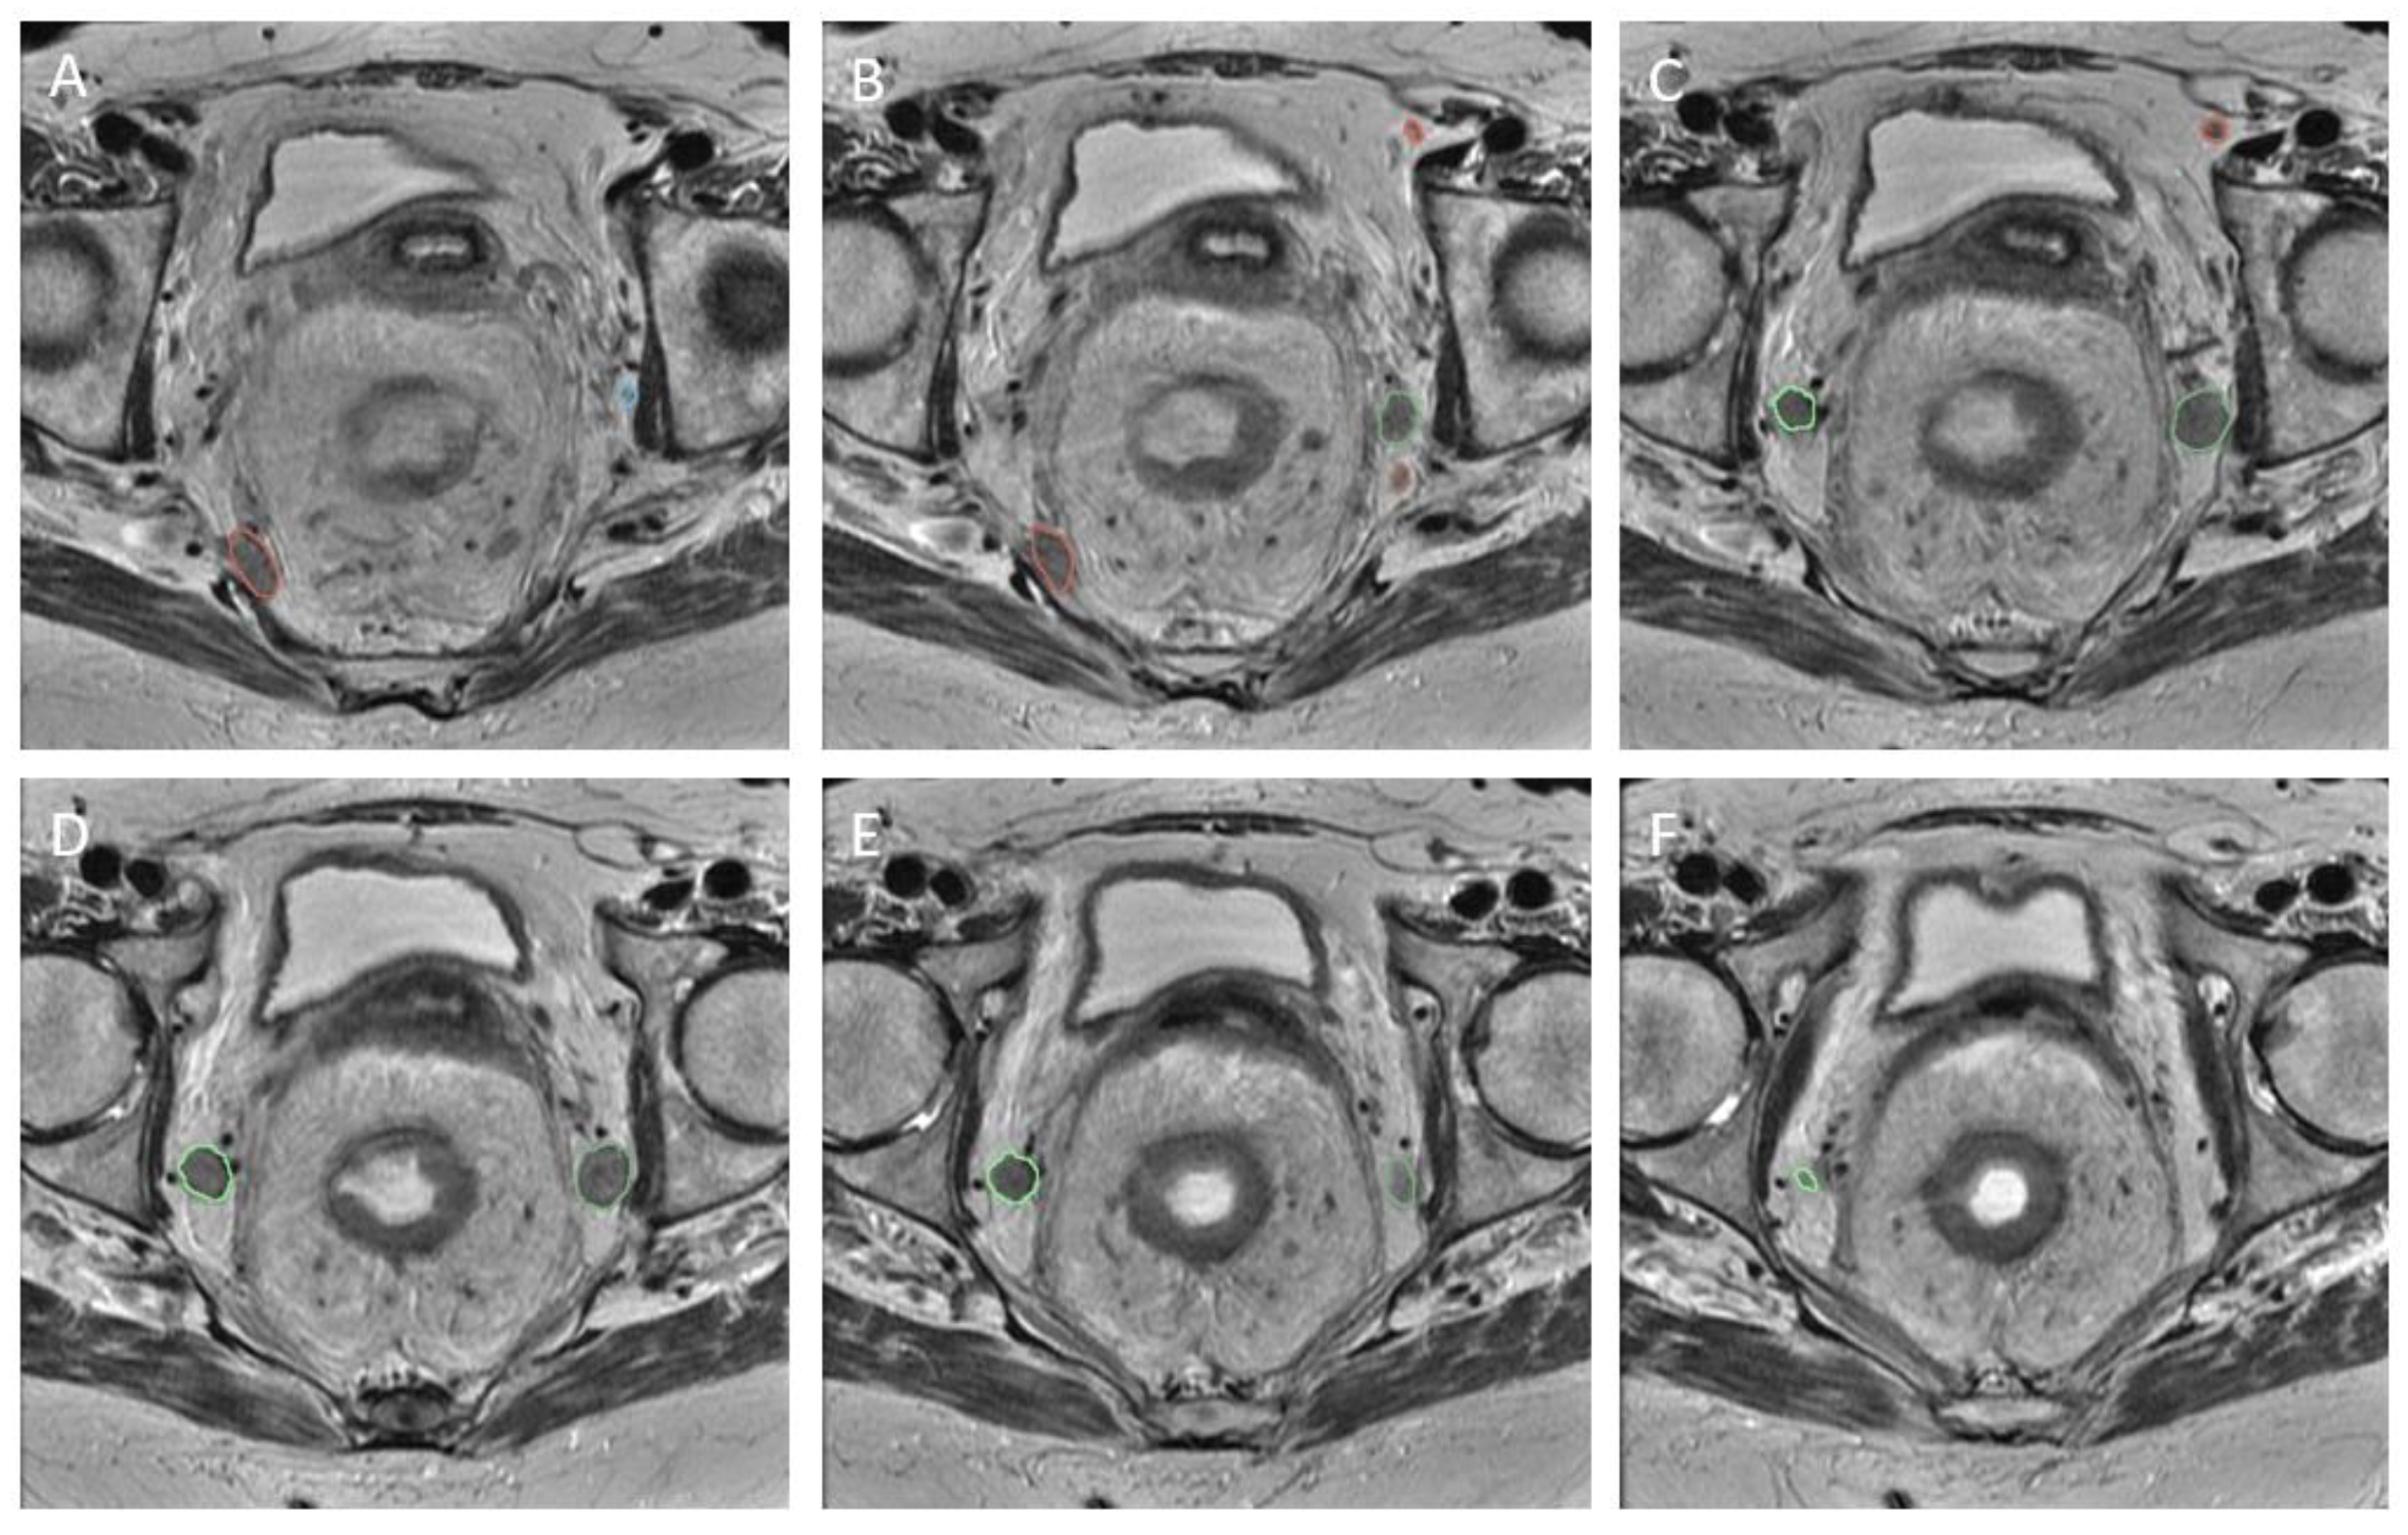

The LLNs documented during re-review were identified by the central researchers in order to establish a region of interest (RoI). In an attempt to avoid intra-observer bias and limit variation, two independent assessors evaluated the scans (T.C.S., M.H.). If the LLN was not easily identified, a senior researcher (M.K.) was contacted for advice. The RoI was created using segmentations (Figure 3) made on the transverse planes of T2-weighted MR imaging, with a maximum slice thickness of 5 mm. All visible LLNs were manually delineated on all slices of the MRI, checked by two researchers, and labelled on the primary and restaging MRI (Figure 3), using 3D slicer [18]. This segmentation distinguished the RoI from background tissue at the voxel level. This resulted in the creation of a binary mask with the same dimensions as the original image for each node.

Figure 3.

Segmentation. Caudal progression through T2 transversal MRI scan (from A–F). Five labelled LLNs.